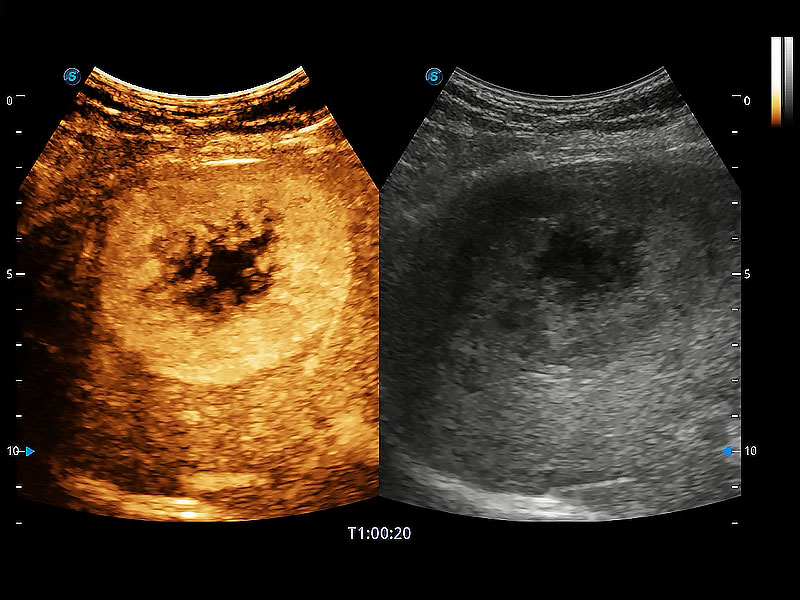

高性能和先进的临床应用工具可以为动物医生提供临床信心。ProPet 80 搭载了先进的腹部和浅表应用工具,帮助医生在日常临床实践中发挥前所未有的作用。

极大提升超低速微细血流的检出能力,同时更精准地滤除软组织和超声信号,为兽用医生提供以往无法通过常规血流获得的疾病诊断信息。

在传统二维血流成像的基础上,呈现血流的立体感,具有动感的生命力之美。即便是微小的血管也能轻松应对,提高了血流的视觉敏感性。

非线性融合造影成像充分利用谐波和基波信号,为难以观察的血流进行增强显像。可用于线阵、凸阵、微凸阵、相控阵探头。